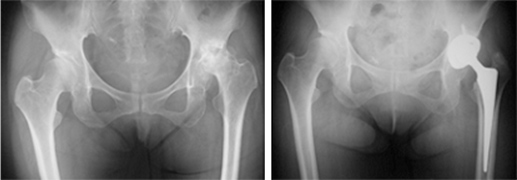

関節リウマチ:関節リウマチ(RA)患者の予後を向上させるために、早期診断は極めて大切です。現在当チームではRA診療に関節エコー(図1)を積極的に導入し早期診断・早期治療を実践しています。RA治療の4本柱は薬物療法、手術療法、リハビリテーション、生活指導であります。発症早期から適切な薬物療法を行うことにより、滑膜炎と骨破壊の進行を抑制するよう取り組んでいます。一方滑膜炎が沈静化しない場合や関節破壊が進行してしまった場合にはタイミングよく外科的治療を行う必要があります。当チームで行う手術としては人工股関節置換術(図2)、人工膝関節置換術、膝滑膜切除術、人工足関節置換術(図3)、足関節固定術、前足部矯正骨切り術、前足部切除関節形成術、人工肩関節置換術、人工肘関節置換術(図4)、肘滑膜切除術、手関節形成術、手関節固定術などがあります。また生活指導とリハビリテーションはRA患者のQOL維持のために極めて重要であり、全経過を通じて行う必要があります。RA指導医および専門医が診断から治療まで総合的な知識と技術をいかしてトータルマネージメントを実践しています。

図2